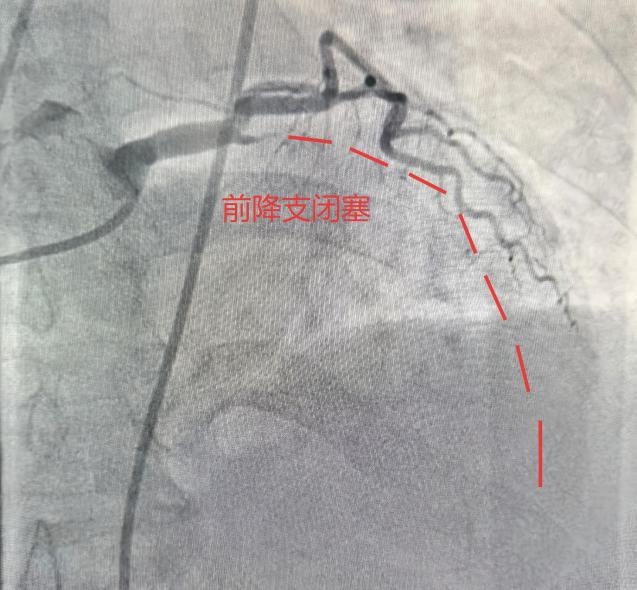

合肥市第三人民医院心血管内科副主任医师樊宗成向908新媒体讲述了当时的细节。急救人员测血压低,做心电图提示:急性广泛前壁心肌梗死!120通过胸痛中心绿色通道将她直接被送入导管室,冠脉造影显示,她的前降支(心脏最重要的血管之一)已经完全闭塞。植入支架、开通血管……经过近40分钟的抢救,她终于转危为安。周阿姨怎么也想不通:最冷的冬天感冒都没有,反而在春暖花开的3月住进了医院?这就是春天,一个万物复苏,却也暗藏“心”机的季节。